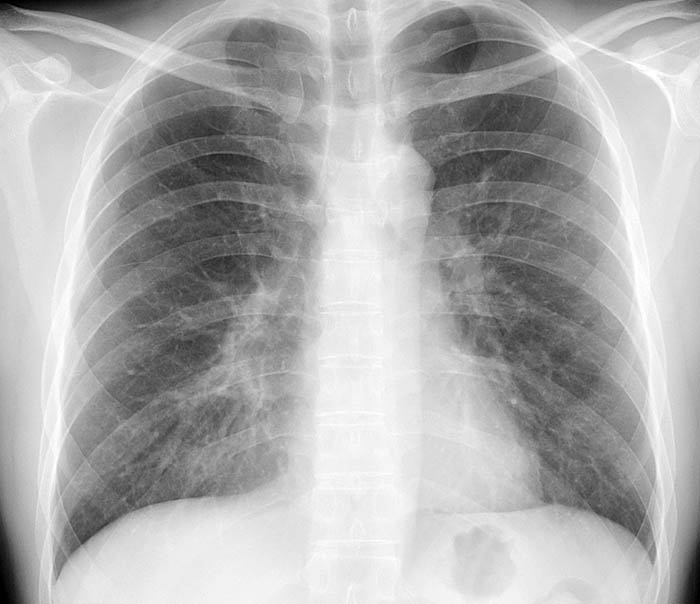

マイコプラズマ肺炎 流行?

今日はちょっとまじめなお話しです。 寒くなってきました。インフルエンザに罹患される方もそろそろ出てきていますが、当院では11月からマイコプラズマ肺炎の患者さんが急増しています。11月から12月第1週までで、当院を受診した咳を主訴とする看者さんのうち、57名の方がマイコプラズマ肺炎と診断されています。

マイコプラズマ肺炎は肺炎マイコプラズマという病原菌による感染症です。死亡に至ることはまれですが、1週間以上咳が持続し、そのあと38度台の発熱があるのが一般的な症状です。

マイコプラズマ肺炎の問題点は感染力の強い病原菌であり、家族内感染や職場内感染が非常に多いということです。適切な抗生剤を内服すれば{効果の無い抗生剤もあるので注意)、治せる病気です。

1週間以上咳が続く方、周囲に咳の持続する方がおられ、ご自身も咳が続く場合にはぜひ医療機関を受診して下さい。